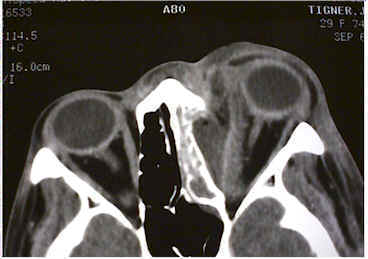

CT of orbit and sinuses to confirm sinus disease, rule out mass, rule out orbital foreign body if h/o trauma (even remote), rule out orbital or subperiosteal abscess, which will require surgical drainage

- CT of orbit and sinuses to confirm sinus disease, rule out mass, rule out orbital foreign body if h/o trauma (even remote), rule out orbital or subperiosteal abscess which will require surgical drainage